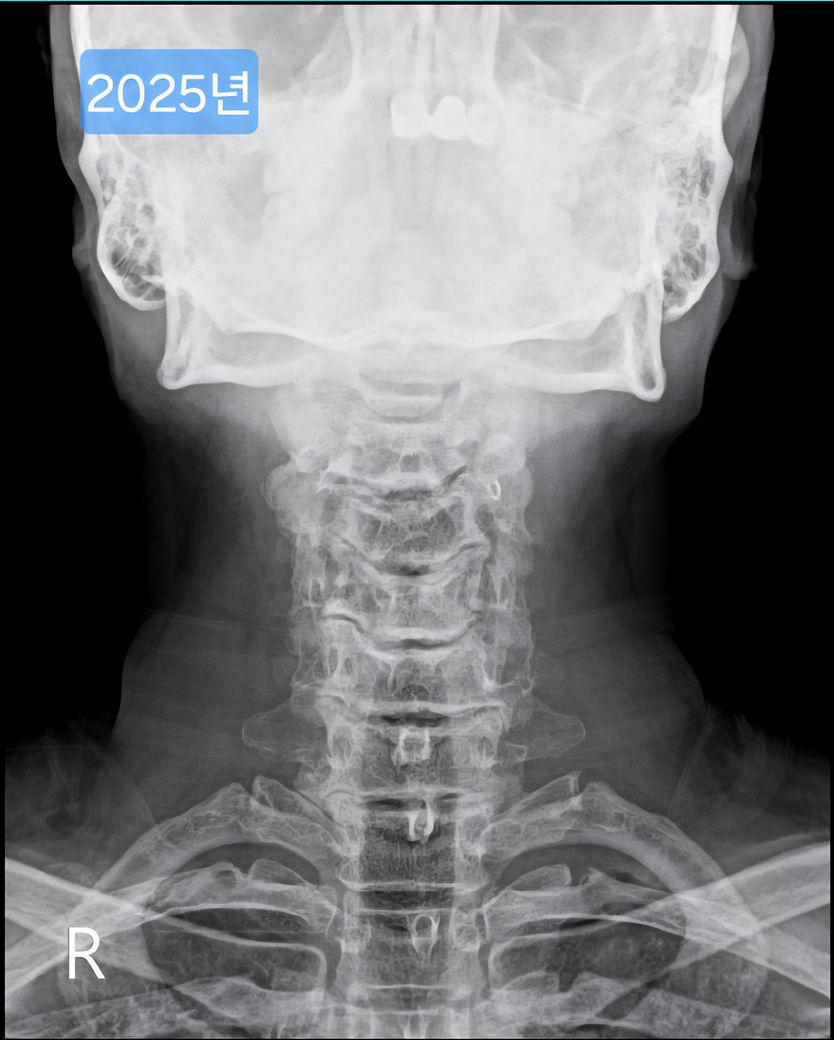

목 엑스레이 사진입니다. 많이 심각한걸까요?

오늘 찍은 2025년도 엑스레이와 9년전 사진을 업로드 해 드리겠습니다.

(이미지에 좌측상단에 해당연도 표시했습니다.)

1. 2016년과 2025년도 목이 상태가 많이 변했나요?

제가 보기엔 9년전에도 경추사이 간격이나 일자목이나 비슷한듯 보여서요.

->우선 사진상으로 봤을 땐 과거에도 충분히 경추 사이의 간격이 좁고, 목의 커브는 C자의 만곡 보단 일자목과 비슷해보이며 시간이 지나면서 누구나 겪는 퇴행성의 과정으로 보여집니다.

9년 전과 비교했을 때 경추 간격과 일자목 형태가 크게 달라진 것 같지 않아 상태가 오래 유지 된 것으로 보입니다. 오랫동안 비슷한 형태라면 큰 통증이나 신경 증상이 없다면 생활에 지장을 주지 않는 범위일 수 있습니다.